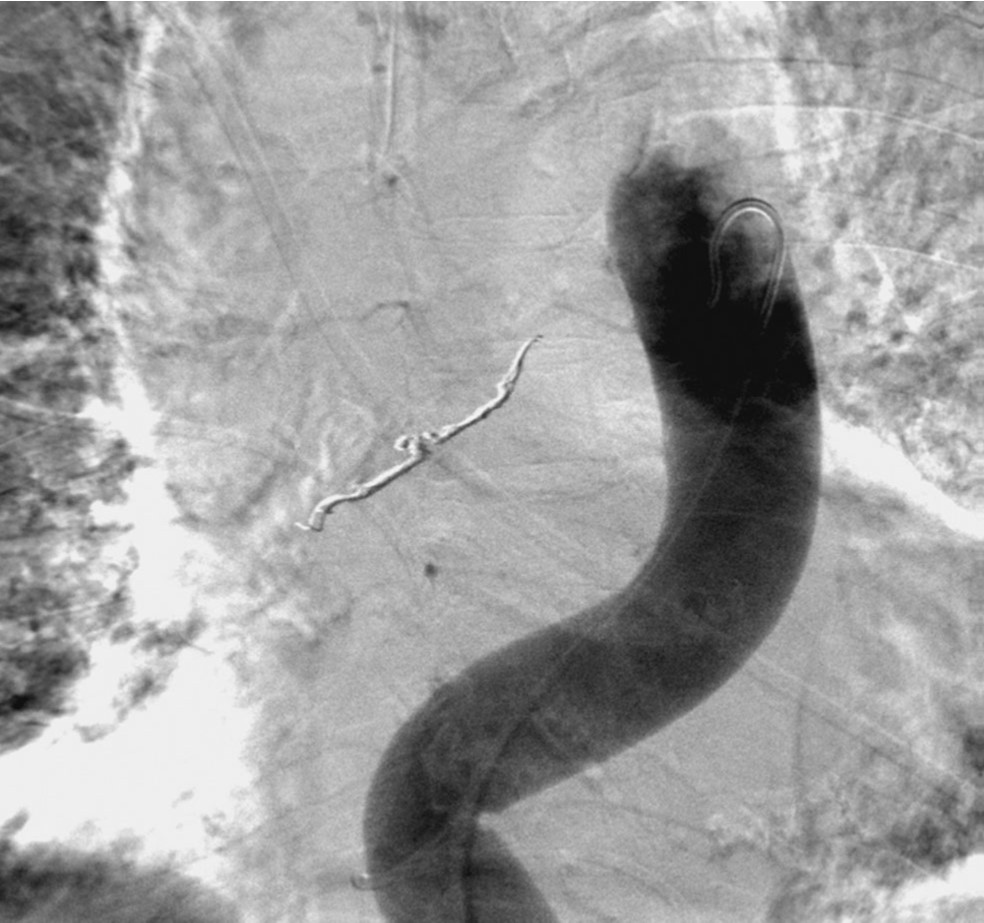

우총대퇴동맥을 통해 5F sheath를 삽입하였다. 5F flush catheter를 대동맥궁에 위치시켜 대동맥조영술을 시행하였고, 대동맥조영술에서 흉부 정중앙에 둥근 모양의 동맥류로 추정되는 병소가 관찰되었음(Fig. 3A). 5F bronchial catheter를 이용해 선택적 우기관지동맥조영술을 시행하였고, 우기관지동맥의 중간 부분에 위치한 동맥류를 확인할 수 있었음(Fig. 3B). 2.0F Progreat microcatheter(Terumo, Tokyo, Japan)를 이용하여 우기관지동맥 동맥류의 원위부까지 진입하였고, 총 9개의 3mm x 2cm Tornado coil(Cook, Bloomington, USA)을 이용하여, 동맥류의 원위부부터 근위부까지 색전을 시행하였다. 색전술 중 동맥류로 추정되는 병소로부터 조영제 유출이 있었고, 코일의 일부가 파열된 동맥류로 돌출하는 것을 볼 수 있었다(Fig. 4). 이후 우기관지동맥의 근위부에서 gelfoam을 이용하여 추가로 색전술을 시행하였다. 이후 시행한 선택적 우기관지동맥조영술 및 대동맥조영술에서 동맥류의 완전 차단과 더 이상의 조영제 유출이 없는 것을 확인하였다(Fig. 5)